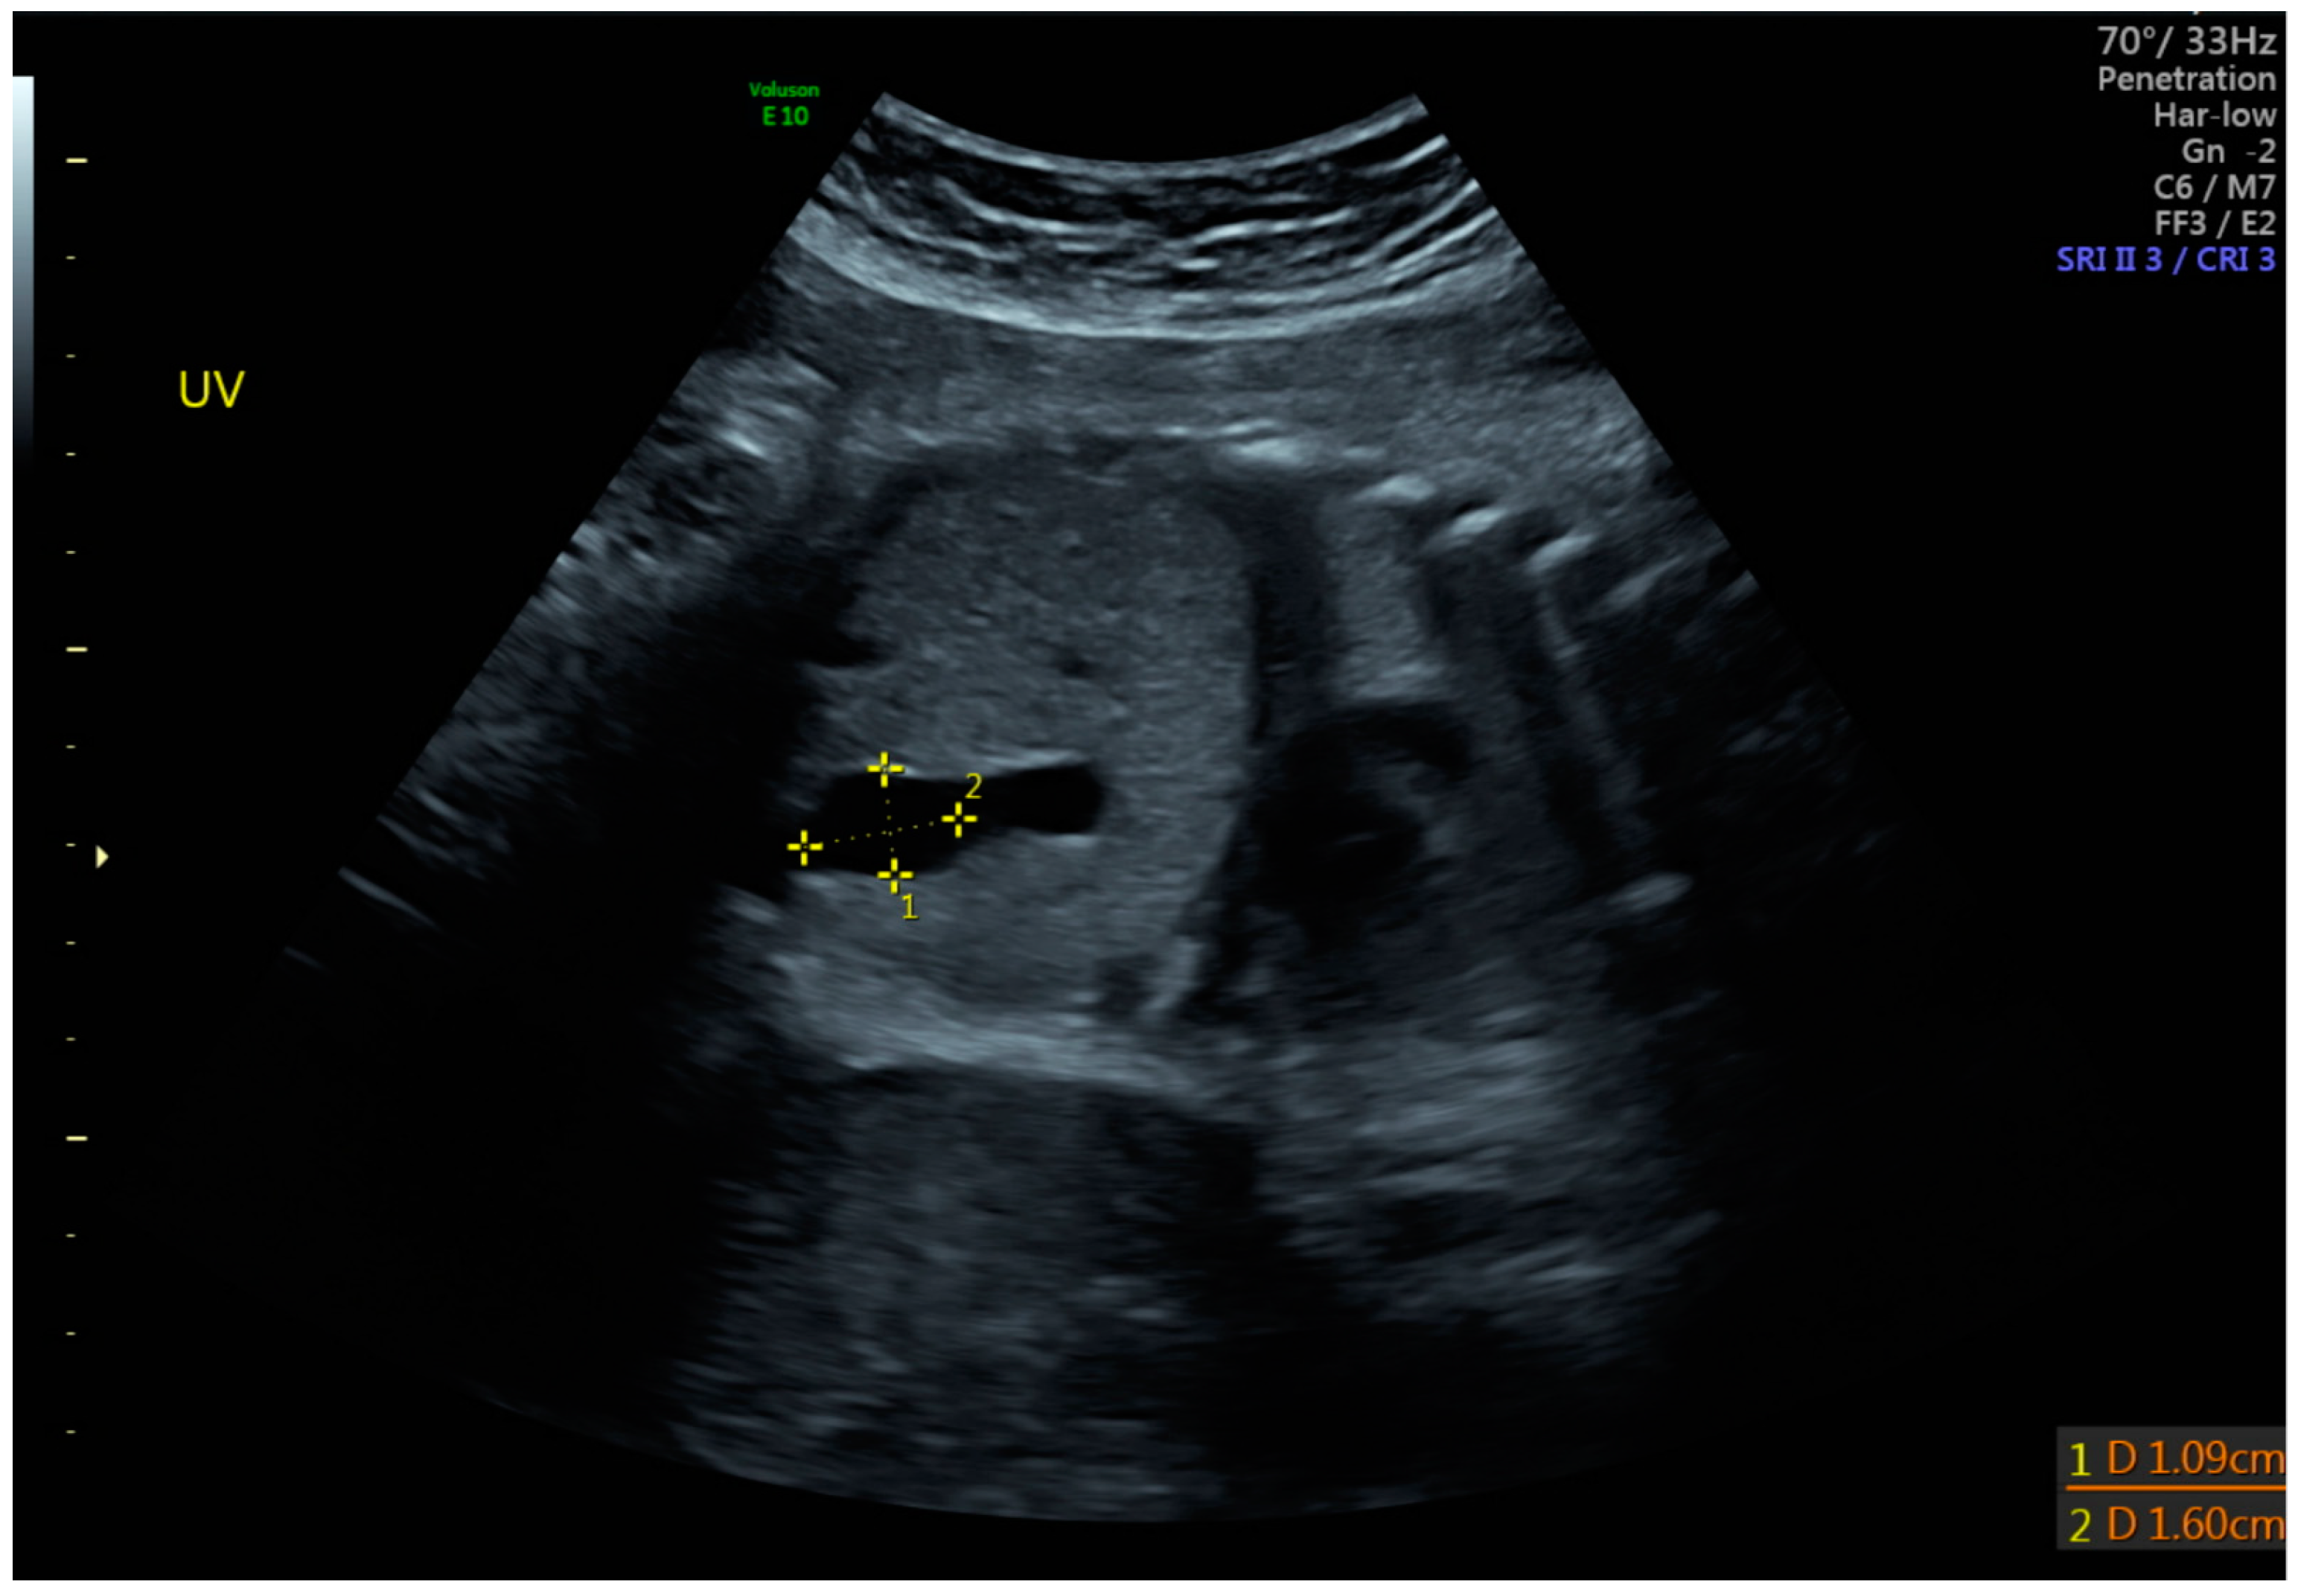

3. Diagnosis

| Largest diameter (mm) | 12.85 | 2.79 |